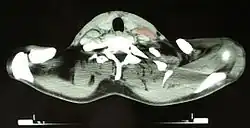

Masywne zajęcie węzłów chłonnych przytchawiczych, wnęki płuca i podostrogowych, zajęcie kręgów

Nacieki chłoniaka Hodgkina w śledzionie